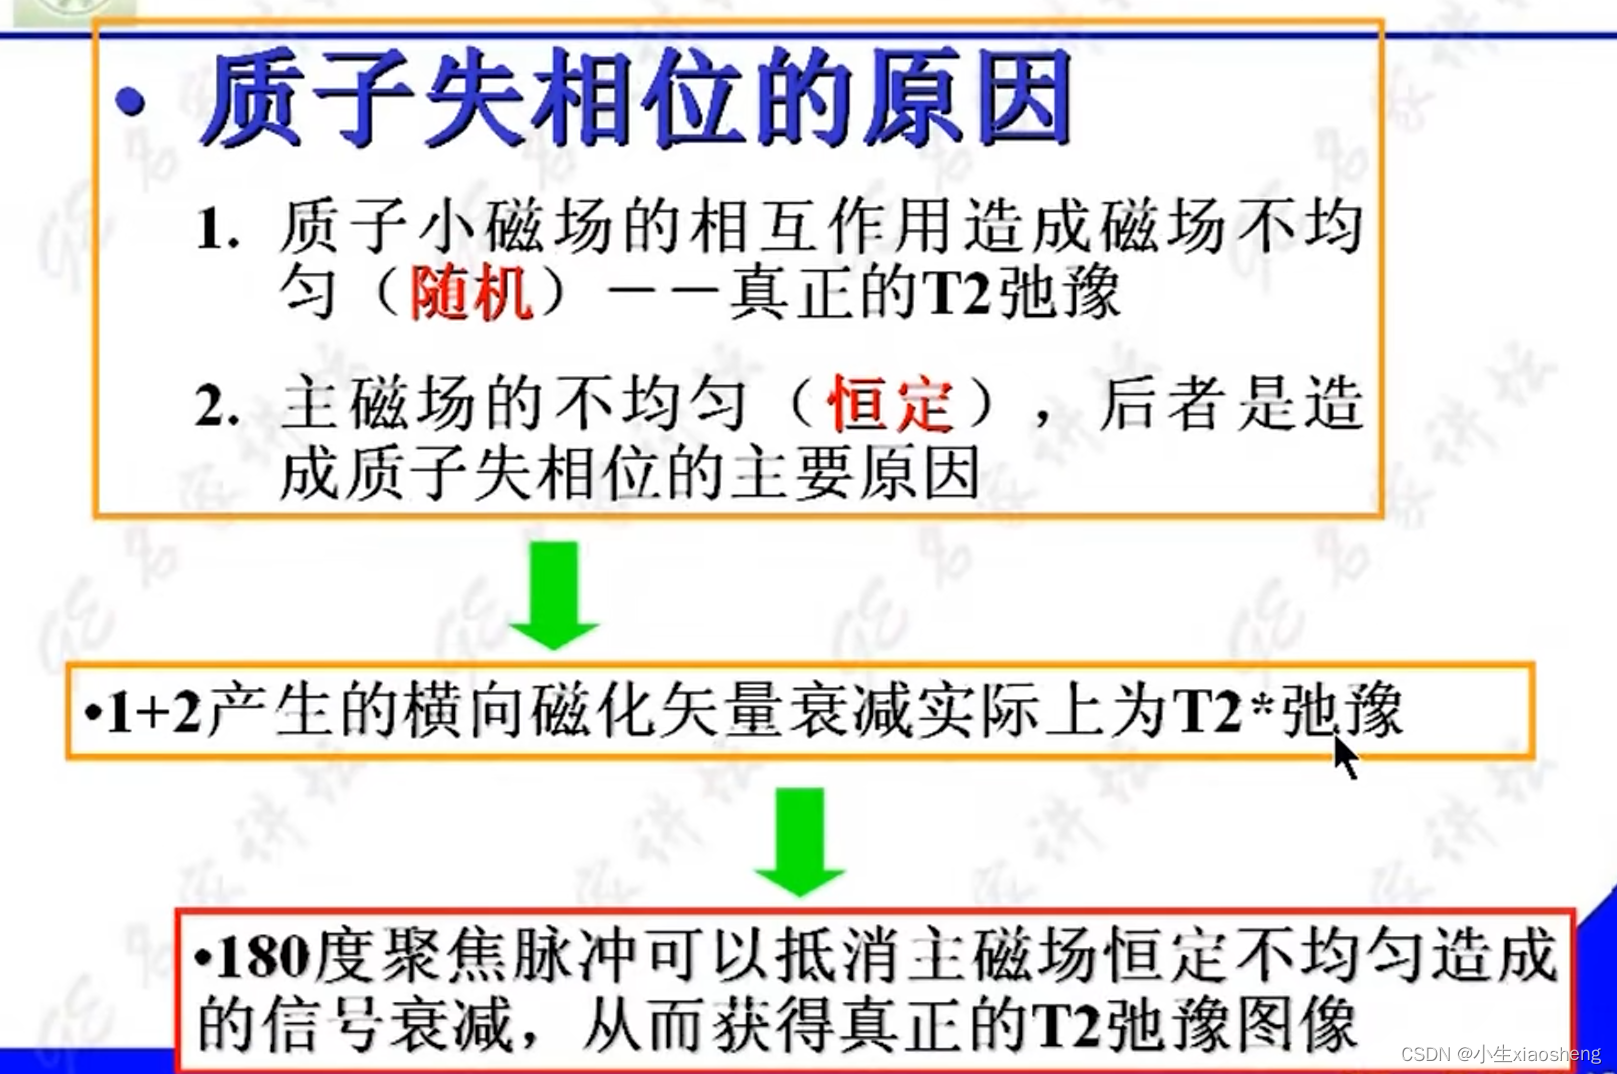

T2(横向弛豫时间):关闭射频脉冲后,质子不再处于同步、同相位状态,指向同一方向的质子散开,导致横向磁化矢量从最大衰减到零。这个过程被称为横向弛豫。

180度的意思就是改变终点的方向,恢复慢的离终点近,恢复快的离终点远,到时候一起到。这样就比原来的弛豫下降的时间要长了。